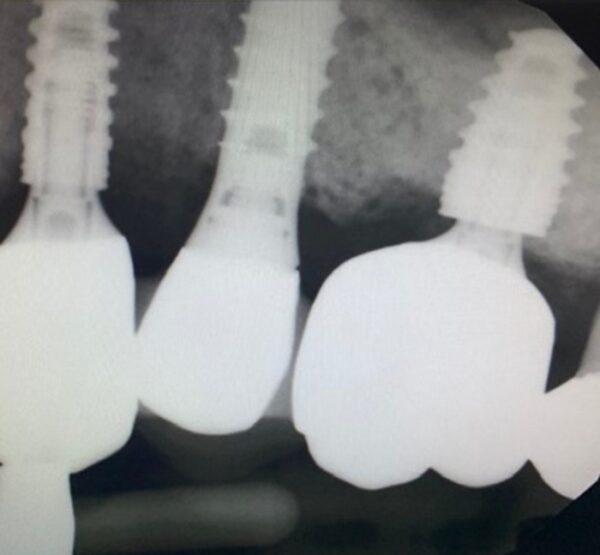

The patient presented upon referral from his periodontist for retrieval of a fractured abutment from a Neodent CM 5×8 implant in the #14 site. There was a prior retrieval attempt by another dentist in the periodontal office, but the fractured abutment could not be recovered. The case presented with an access hole to access the abutment screw through the existing crown with the crown very mobile and being held in place with just the screw. After explaining the recovery steps for this situation, the screw head was accessed in preparation to cut the screw head off as this is the first retrieval step. With the crown recovered, the abutment screw was rotated up as high as possible and then cut off at the level of the abutment fracture. The screw was then allowed to go down and the shaft of the screw was shortened to create 3mm of throughbore space in the retained abutment fragment. The abutment fragment was then tapped to M1.8 and a custom distraction bolt was inserted, and a distraction nut was tightened which released the abutment fragment. The remaining portion of the abutment screw was then retrieved, the implant was cleaned, and the supplied healing abutment was placed finger tight. There was no visible implant damage as view at 25x from either the fractured abutment or any of the retrieval efforts so the prognosis going forward is unchanged.

The Neodent CM implant is basically a copy of the Ankylos implant in regard to the conical interface dimensions. However, there is a notable difference in the throughbore diameter and the resulting abutment wall thickness. Specifically, the Ankylos CX implant has a 2.5mm OD diameter as it exits the implant top and has a throughbore diameter of 1.18mm. Simple math yields a titanium cross-section of 3.97 sq. mm. This Neodent CM implant also has a 2.5mm abutment exit diameter but this recovered throughbore measured out on my optical comparator at 1.5mm. Again, applying the math, the titanium cross-section would be 3.143 sq. mm. (This is almost identical to the Bicon 2mm solid abutment.) However, in this case, the abutment fractured just below the implant top. Measuring the actual fracture zone on the recovered crown on the optical comparator the story became worse. The OD of the abutment at the fracture site was 2.438mm with a throughbore diameter of 1.5mm which calculates to 2.9 sq. mm of titanium on the fractured site. This is the lowest number I have seen to date on any of the fractured abutments I have recovered and evaluated, with the possible exception of some TiBase abutments. This absolutely explains why the fracture occurred in the Neodent CM single molar application if titanium cross-section dimension correlate with fractures. I absolutely believe it does, so I would expect them to occur as frequently or possibly more frequently than in the Ankylos system, and that is hard to believe, as I have seen over 200 Ankylos abutment fracture cases to date. This also explains why the Neodent GM line was created which has a larger diameter conical connection (3mm), although the same connection is still used in all implant diameters. To give you some perspective on the numbers here is a partial list of some of my abutment cross-section data at implant top where these fractures have occurred: